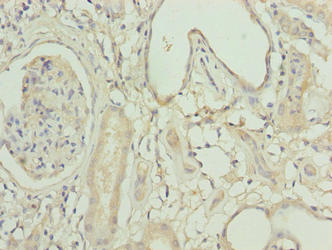

圖片:

應用范圍:ELISA, IHC

Application Recommended Dilution IHC 1:20-1:200 -